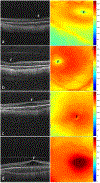

Methods: We imaged both eyes of preterm infants with an investigational noncontact, handheld swept-source (SS) OCT at the time of clinical ROP examinations. Macular OCT features and layer thicknesses for untreated eyes of infants at 36 ± 1 weeks' PMA were compared with demographic data and clinical ROP examination performed by experts. Statistical analyses accounted for the use of both eyes of infants.

Results: We captured macular OCT from 169 eyes (1 eye excluded because of prior ROP treatment) at 36 ± 1 weeks' PMA. The quality of OCT volumes was excellent in 33 eyes (19%), acceptable in 112 eyes (67%), poor in 24 eyes (14%), and unusable in 0 eyes (0%). Macular edema was present in 60% of eyes and was bilateral in 82% of infants with edema. At the fovea, retinal and inner nuclear layer thickness increased with edema severity: 183 ± 36 μm and 51 ± 27 μm in mild (16% of eyes), 308 ± 57 μm and 163 ± 53 μm in moderate (25%), and 460 ± 76 μm and 280 ± 83 μm in severe edema (12%), respectively. With an increase in ROP stage from 0 to 2, the mean ± standard deviation retinal thickness at the fovea increased from 227± 124 μm to 297 ± 99 μm (P < 0.001). The choroid was thinner, 155 ± 72 μm, with preplus or plus disease versus without, 236 ± 79 μm (P = 0.04), whereas retinal thickness did not vary.

Conclusions: We demonstrated the reliability of methods and the prevalence of OCT findings in preterm infants enrolled in BabySTEPS at a single time point of 36 ± 1 weeks' PMA. Variations in layer thicknesses in infants at this time point may reflect abnormalities resulting from delay in foveal development that may be impacted by macular edema, ROP, or both.